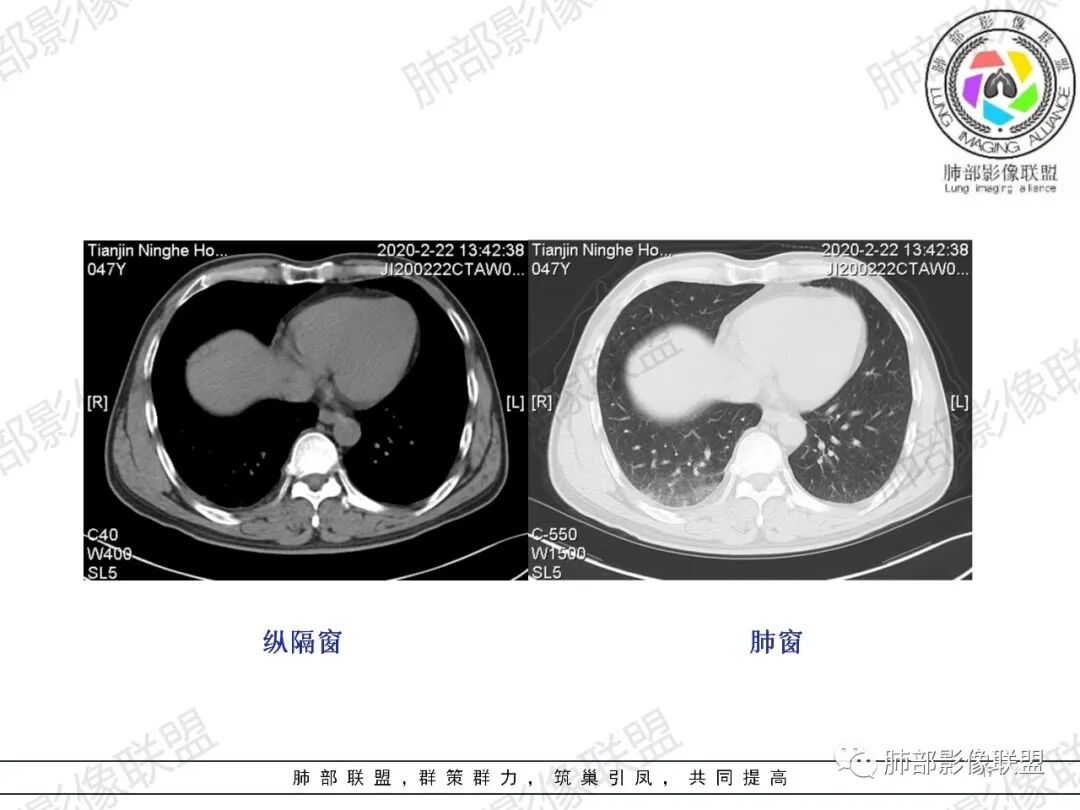

马春平(张家港市一院胸外科):中年男性、低热、痰血、胸痛 、血象高,右上叶多发结节、疑似空洞、渗出、纤维条索、树芽,右下肺胸膜下与胸膜平行GGO肺泡和小叶间隔增厚,考虑二元论:右上结核、右下肺梗

一切∮随缘:右肺肺尖段多发结节片状高密度影,部分伴有反晕征,边界欠清楚,部分伴有纤维索条,支气管显示欠佳,小叶间隔增厚,周围血管束增粗,(考虑结核可能)右肺下叶胸膜下片状磨玻璃影,与胸膜相贴,与肺组织交界面清楚,实性偏少,考虑:肺栓塞?病毒?OP?

王秀仙:右肺上叶可见结节及斑片影,部分呈反晕征,边缘清晰,右肺下叶后基底段胸膜下磨玻璃样实变影,呈扇形,内部见细网格,右肺上叶考虑结核。右肺下叶考虑肺栓塞,鉴别病毒肺炎。

小兜:男,47岁,胸闷气短入院,一天前无明显诱因胸闷气短伴呼吸困难,夜间出现右侧胸痛,与呼吸及体位有关,曾有一次痰中带血。CT示右肺上叶尖段多发结节,条索影,可见树芽征及反晕征。右肺下叶胸膜下片状密度增高影,宽基底与胸膜相连,成扇形。综合考虑右肺上叶尖段结核可能;右肺下叶肺栓塞?病毒性肺炎?

琦遇:右肺上叶结核基本明确,考虑活动性,有钙化、反晕征、结节、斑片、纤维索条;右肺下胸膜下GGO,内大小网格,胸膜增厚,患者胸痛,咯血,首先考虑PE,下一步增强CTPA以明确

微微笑:右肺上叶斑片、结节、索条影,边缘较清晰,见反晕斑片,考虑结核。右肺下叶宽基底磨玻璃影,网格样改变,胸膜增厚,结合病史,考虑栓塞。

三个石头:右肺上叶结节,斑片,条索,考虑结核。右肺下叶大片磨玻璃,有胸痛,咳血,考虑肺栓塞,建议增强。鉴别病毒肺炎

水晶石头:患者中年男性,胸闷、气促1天。伴右胸痛及痰中带血。否认结核、心脏疾病等病史。查体无特殊。完善血常规白细胞计数、中性粒细胞百分比及C反应蛋白升高。心电图、B超、凝血功能、降钙素原、脑钠肽正常。胸部CT:右肺上叶尖段多发结节、斑片、纤维条索影,见小叶间隔增厚及反晕征。右肺下叶后基底段胸膜下片状磨玻璃影,见小叶内间隔增厚。右侧胸膜增厚,未见明显淋巴结增大。综合考虑右上肺结核病变,右下肺肺栓塞。鉴别病毒性肺炎及恶性病变。

小锁:中年男性患者,急性起病,胸闷气喘伴有胸痛,低热,低氧,白细胞增高。CT:右肺上叶斑片状稍高密度影,粟粒样树芽征,有钙化,考虑继发性结核;右肺下叶肺动脉增粗,溶冰征,提示血管来源病变,结合临床病史,考虑肺栓塞。

然后就是右下叶病灶的问题

后基底段,胸膜下,这个没问题吧

我们看看病变的形态、密度、边缘、内部改变

GGO密度

边缘不清

可惜没有重建,楔形?

细网格明显

支气管通畅,壁增厚

血管增粗